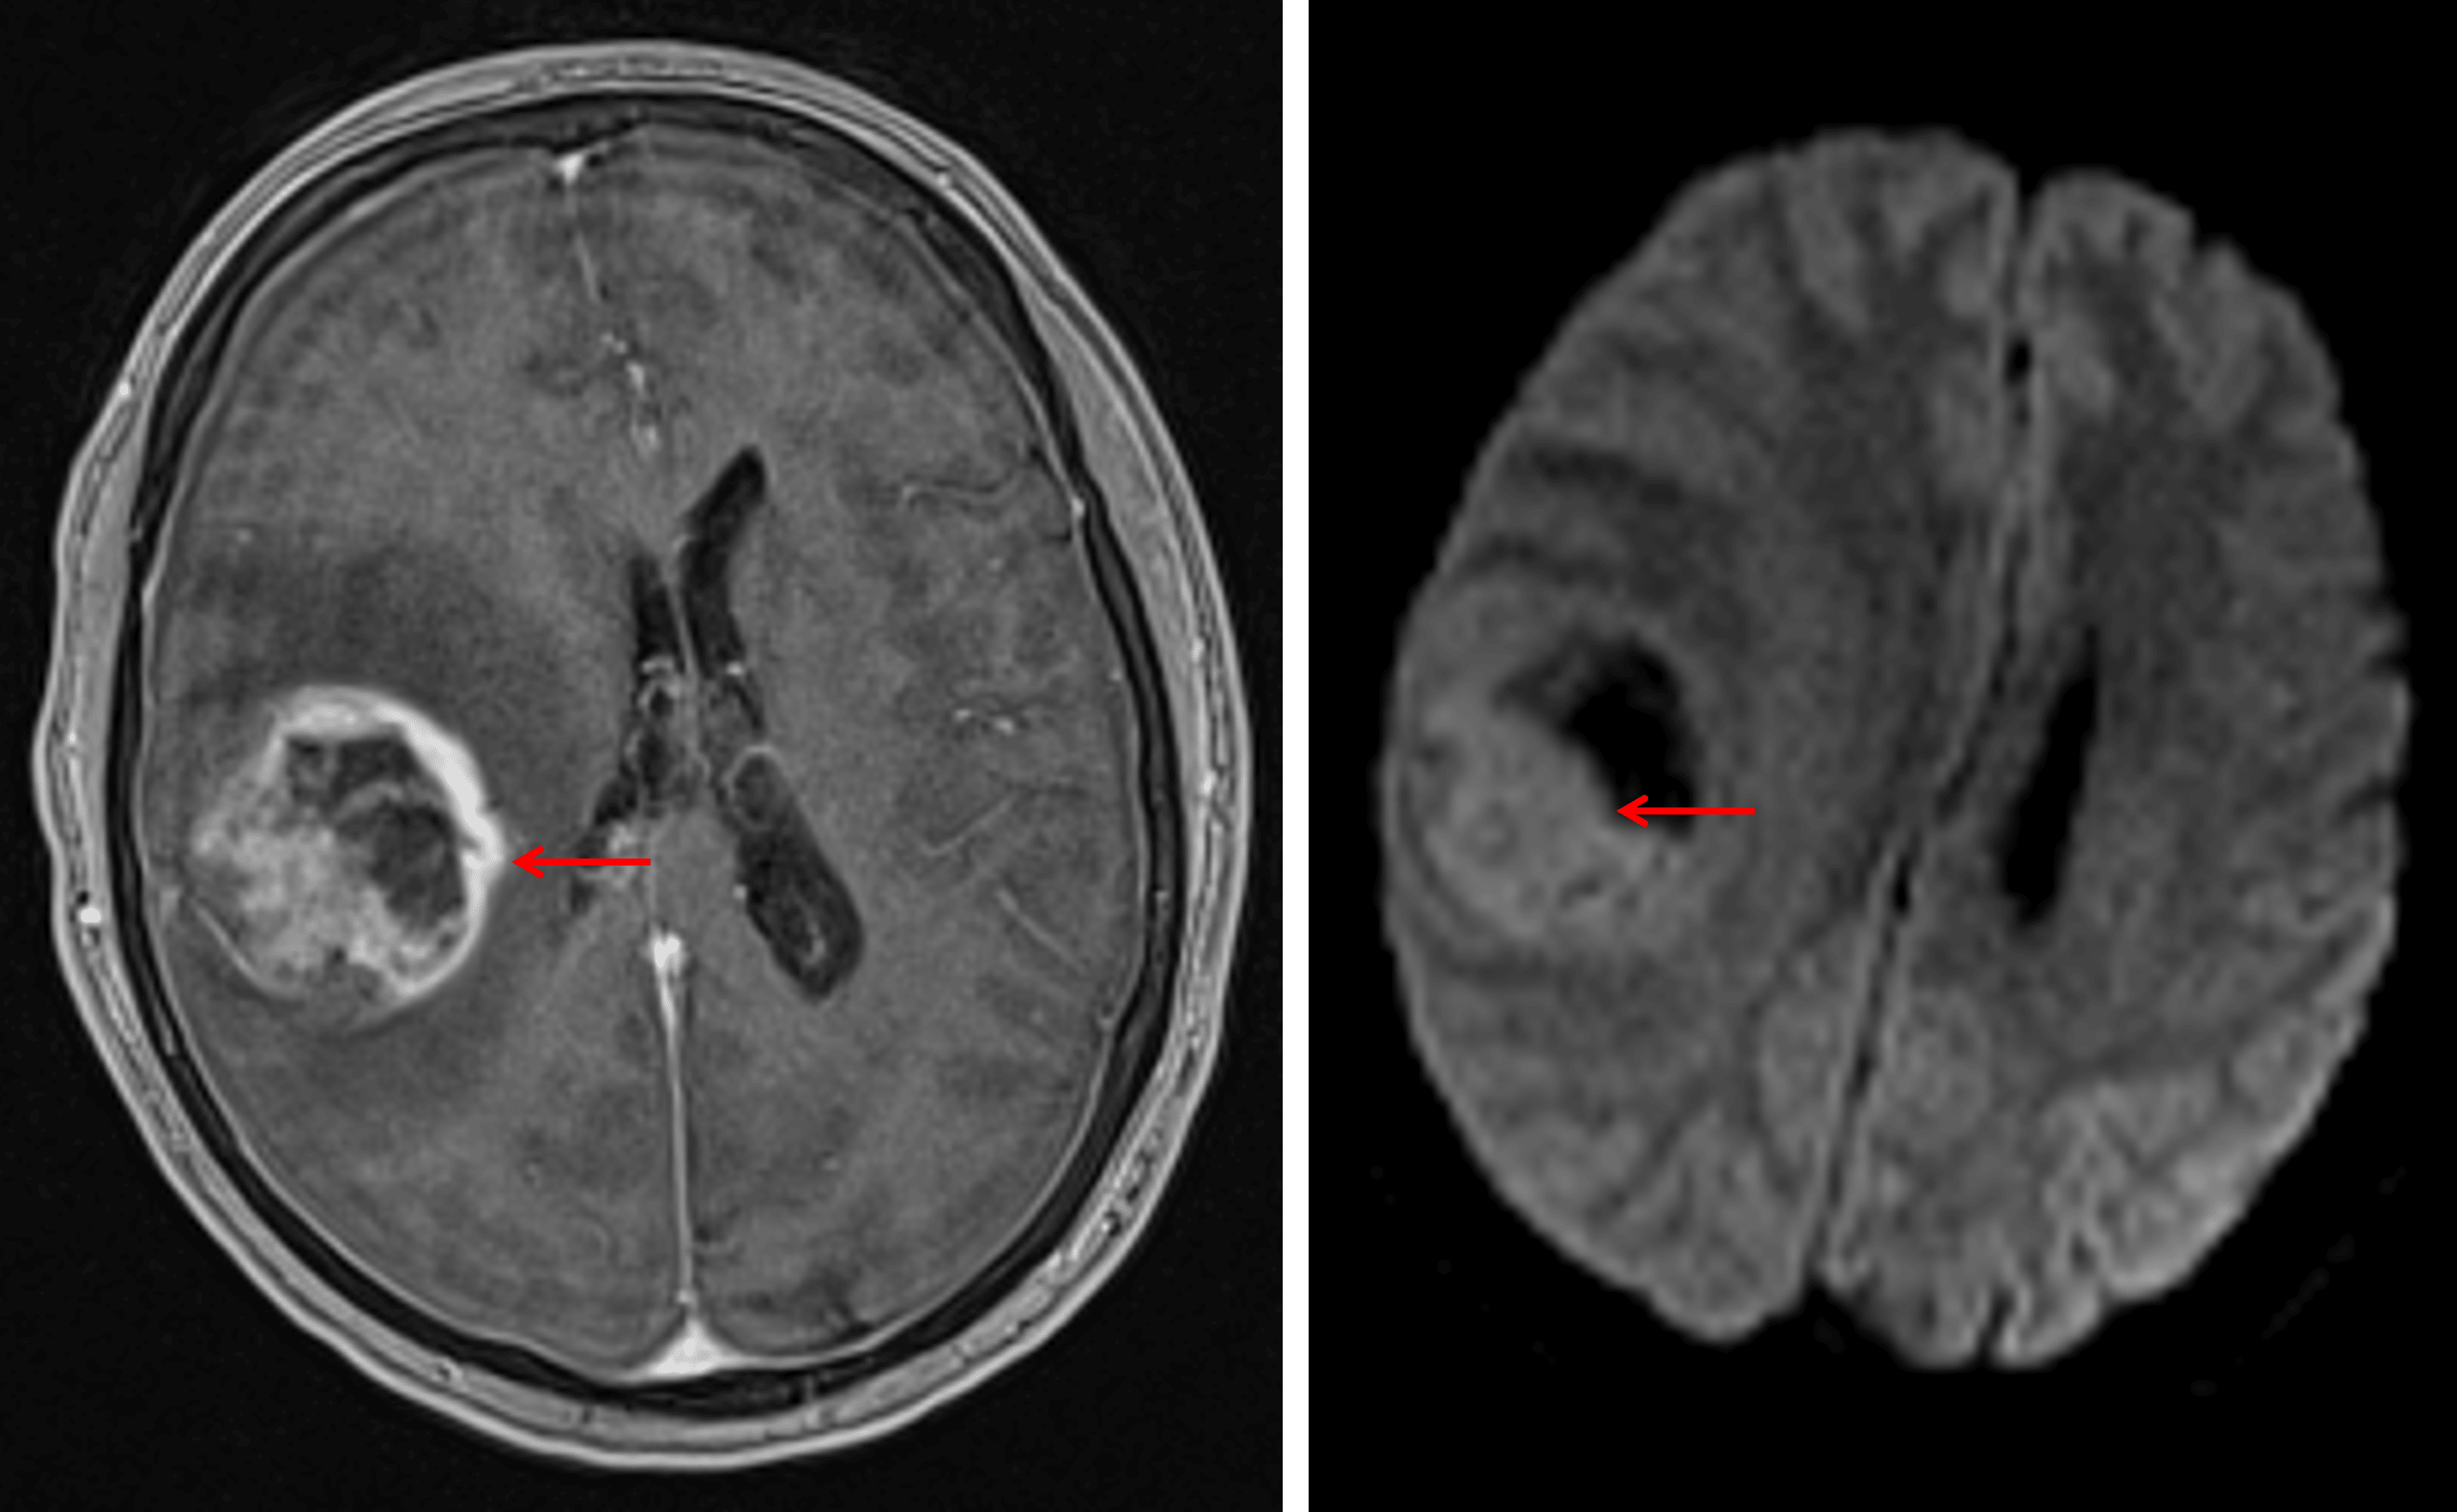

- Large, peripherally-enhancing, centrally necrotic mass bridging the right frontal and parietal lobes measuring 4.5 x 4.2 x 4.5 cm with extensive T2/FLAIR signal hyperintensity in the surrounding white matter

- Restricted diffusion correlating with the enhancing components

- Susceptibility artifact correlating with the area of central necrosis

Heterogeneously enhancing mass with reduced diffusivity corresponding with the enhancing components (red arrows), most suspicious for a high-grade glial neoplasm.